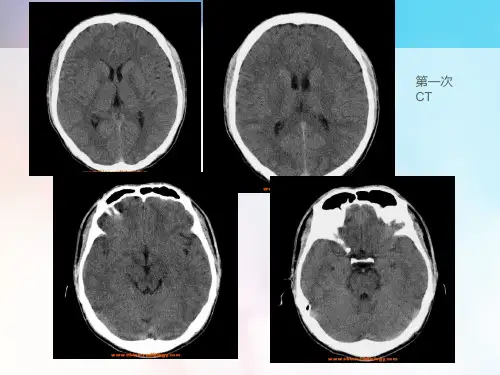

头部CT检查可发现脑部有病理性密度减低区; 脑电图检查可发现中度及高度异常。